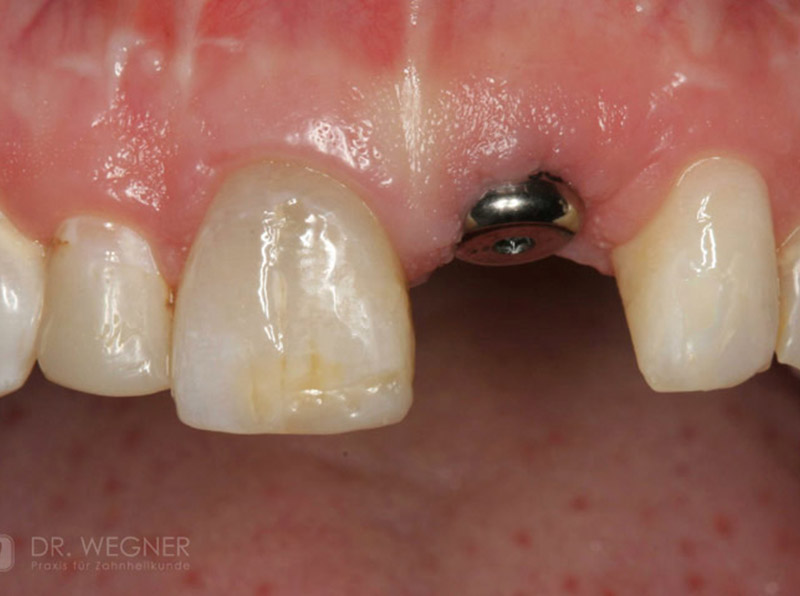

Unter dentalen Implantaten versteht man im allgemeinen eine Schraube, die dort, wo ein oder mehrere Zähne verloren gegangen sind, in den Kieferknochen "eingepflanzt" wird. Diese Therapieform der Implantologie hat sich in den letzten Jahren zu einem alltäglichen Therapieverfahren in der Zahnheilkunde entwickelt. Wissenschaftliche Untersuchungen zeigen hierfür eine Erfolgsquote von i. d. R. 80-98 % über 10 Jahre. Verglichen mit anderen zahnärztlichen Maßnahmen gibt es nahezu keine andere Therapie mit derart guten Erfolgsaussichten. Auch eine Verbesserung der Lebensqualität wird durch implantatgetragenen Zahnersatz laut klinischer Studien erreicht.

Mittlerweile hat sich die Implantologie zu einem alltäglichen Therapieverfahren mit sehr guten Erfolgsaussichten in der Zahnheilkunde entwickelt. Bei guter Mundhygiene und regelmäßigen Kontrolluntersuchungen können fachmännisch gesetzte Zahnimplantate ein Leben lang halten.